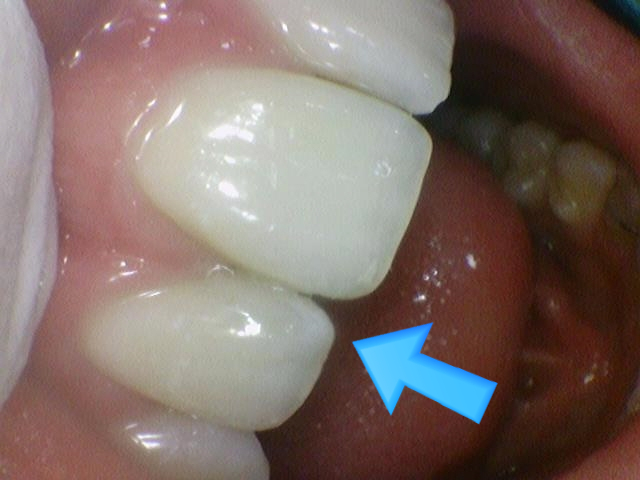

↑치료 후 사진. 매우 감쪽같이 치료되어 외국인환자분이 깜짝 놀라셨습니다.

이렇게 치아 뒤쪽에 기존에 다른 치과 유지장치가 뒤쪽에 있었음에도 레진으로 잘 마무리 할 수 있었습니다.